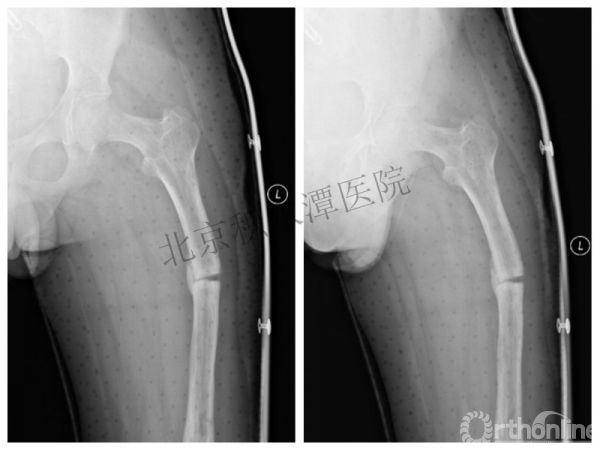

病例分享六

7岁、男孩,桡骨远端骨折

原始损伤片

手法整复后 - 45分钟!

伤后4天复查

伤后30天!

医生的处理方法!——医生终于没有坚持自己的原则!

伤后40天—切开复位内固定!

伤后18个月

如何面对?

心情之压抑无以言表!

手术历时近 5小时!心情之压抑无以言表!因为当时的经治医生是他们的进修生!感觉是他们的失职甚至渎职!

唯一可以肯定—预后不佳!郭教授是党员!是无神论者!但是很诡异的事情:手术中发生—C形臂看不清!拍片条件总是调节不好!手术器械换了三套!内固定钢板总不合适!

术后15月,虽然家长满意了,但是他们医生不满意!